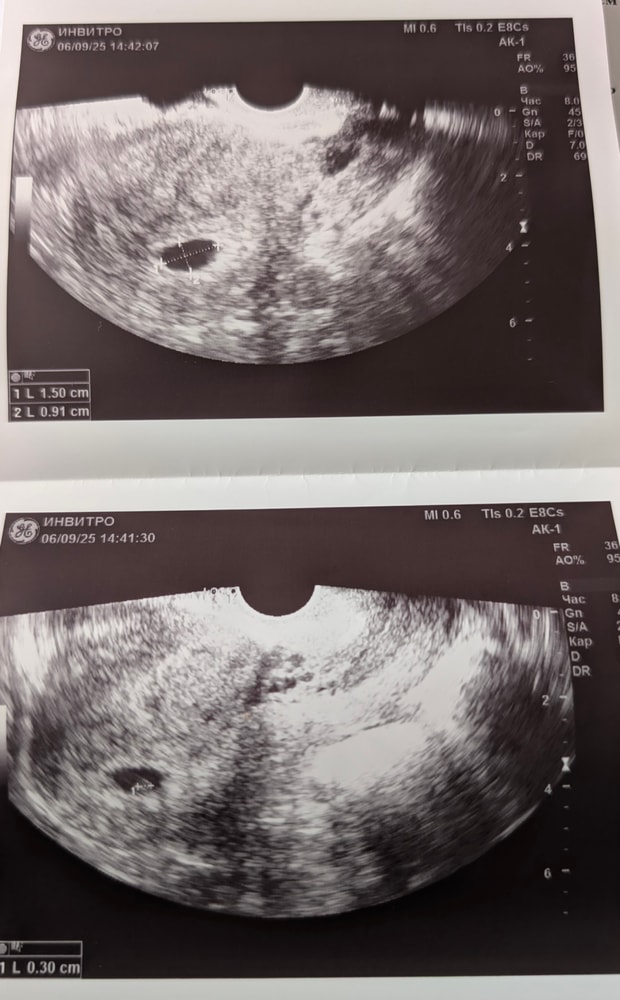

Сходили с мужем на первое УЗИ. По М срок(на 6.09.) - 6 недель 3 дня. Малышок растет. Даже середечко уже билось🥹🥰 Врача выбрала на сайте продокторов, просто по фото. Женщина мне понравилась- Камболова Оксана. Отзывов о ней было не так много, но хорошие. И правда, я не ошиблась, очень приятный человек. На все вопросы отвечала спокойно и вежливо.